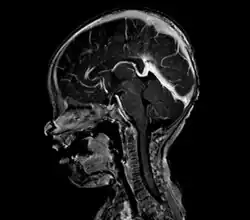

Large arteriovenous malformation of the parietal lobe

A cerebral AVM diagnosis is established by neuroimaging studies after a complete neurological and physical examination.[5][13] Three main techniques are used to visualize the brain and search for an AVM: computed tomography (CT), magnetic resonance imaging (MRI), and cerebral angiography.[13] A CT scan of the head is usually performed first when the subject is symptomatic. It can suggest the approximate site of the bleed.[3] MRI is more sensitive than CT in the diagnosis, and provides better information about the exact location of the malformation.[13] More detailed pictures of the tangle of blood vessels that compose an AVM can be obtained by using radioactive agents injected into the blood stream. If a CT is used in conjunction with an angiogram, this is called a computerized tomography angiogram; while, if MRI is used it is called magnetic resonance angiogram.[3][13] The best images of a cerebral AVM are obtained through cerebral angiography. This procedure involves using a catheter, threaded through an artery up to the head, to deliver a contrast agent into the AVM. As the contrast agent flows through the AVM structure, a sequence of X-ray images are obtained.[13]